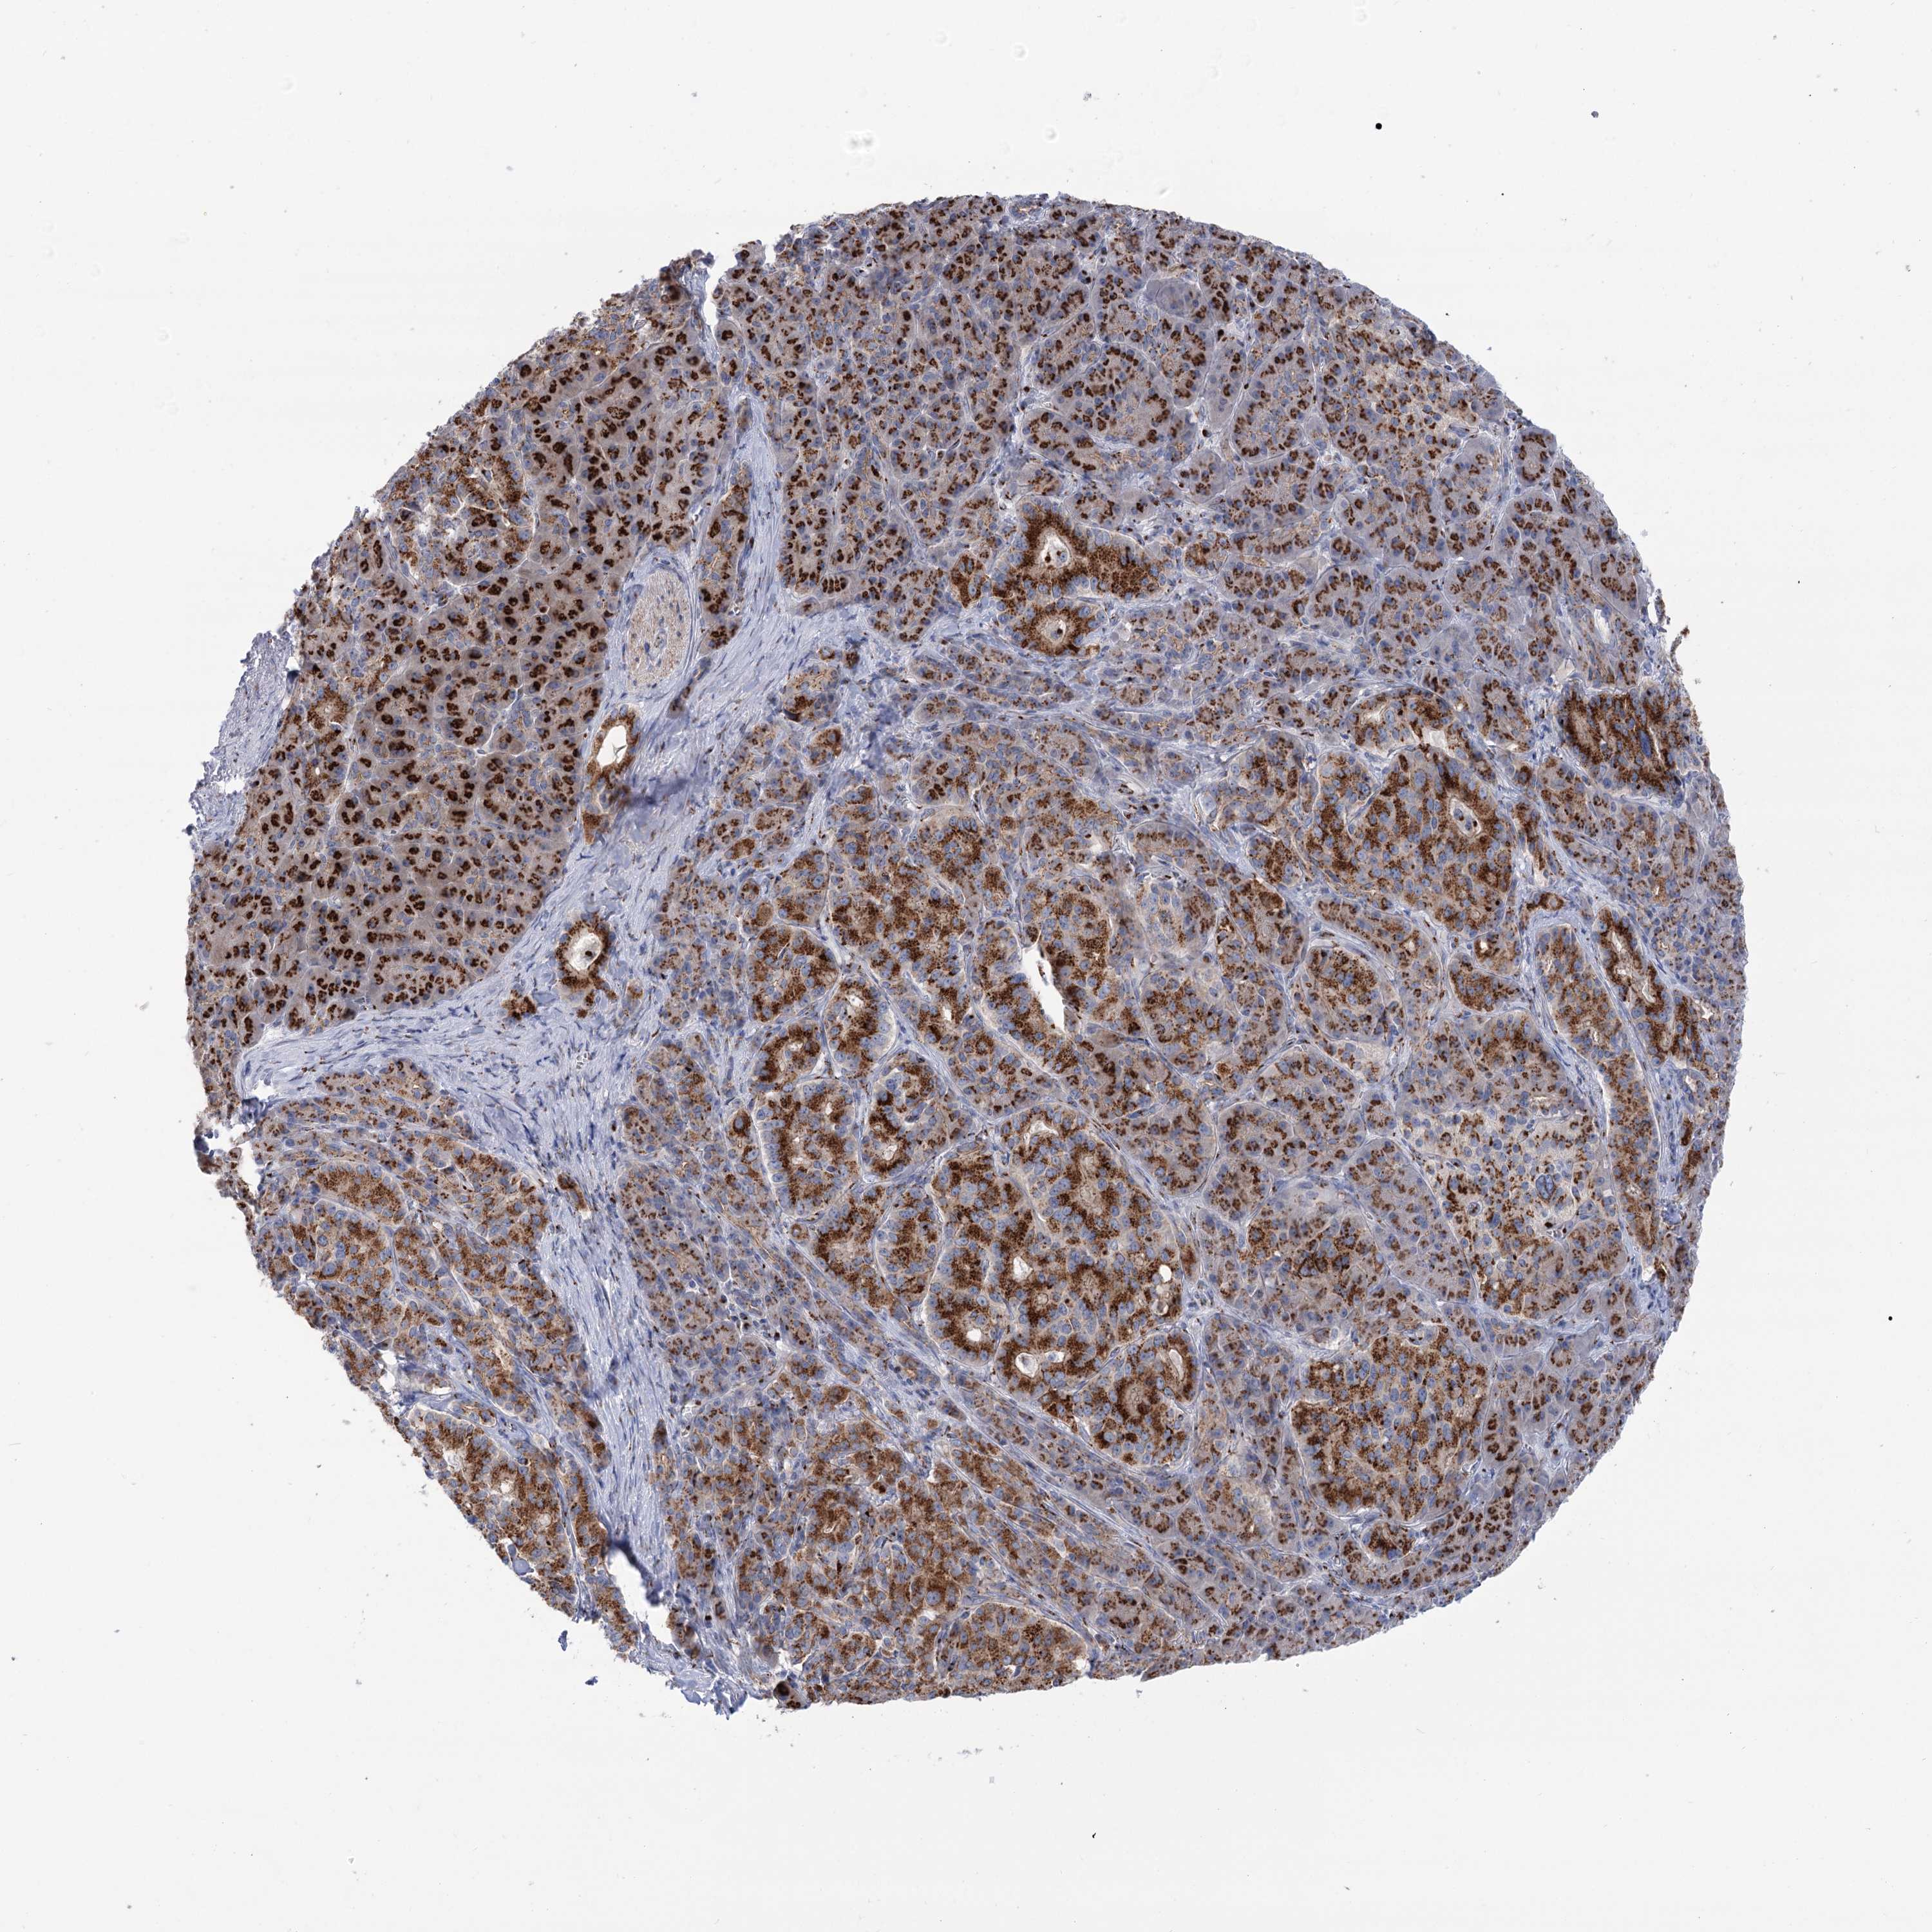

PANCREATIC CANCER - Protein expressioni

A mouse-over function shows sample information and annotation data. Click on an image to view it in a full screen mode. Samples can be filtered based on level of antibody staining by selecting one or several of the following categories: high, medium, low and not detected. The assay and annotation is described here.

Note that samples used for immunohistochemistry by the Human Protein Atlas do not correspond to samples in the TCGA dataset.

Antibody stainingi

Antibody staining in the annotated cell types in the current human tissue is reported as not detected, low, medium, or high, based on conventional immunohistochemistry profiling in selected tissues. This score is based on the combination of the staining intensity and fraction of stained cells.

Each image is clickable and will lead to virtual microscopy that enables deeper exploration of all samples and also displays staining intensity scores, fraction scores and subcellular localization as well as patient and tissue information for each sample.

Antibody HPA038299

Staining

High

Medium

Low

Not detected

Intensity

Strong

Moderate

Weak

Negative

Quantity

>75%

75%-25%

<25%

None

Location

Nuclear

Cytoplasmic/membranous

Cytoplasmic/membranous,nuclear

Adenocarcinoma, NOS